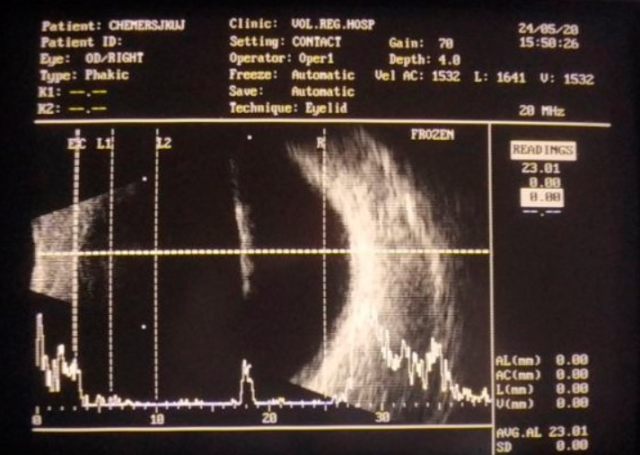

За даними УЗД лікарем Ігорем Стадницьким було з ‘ясовано, що стороннє тіло є досить довгим та проходить в задню камеру ока через весь кришталик.